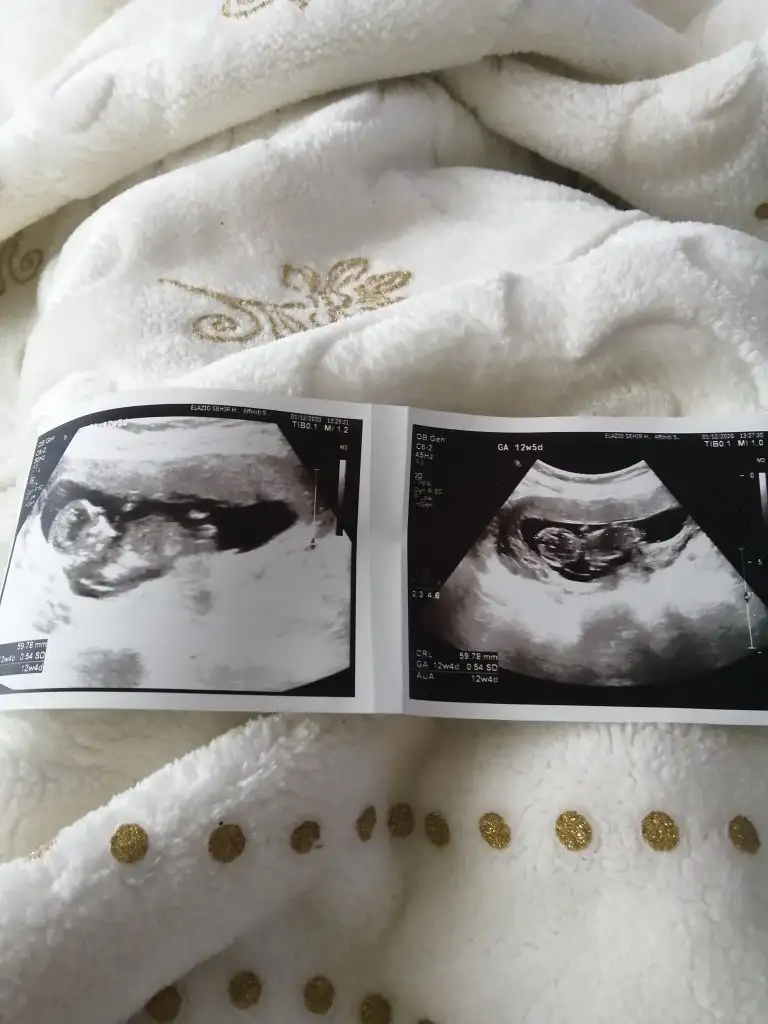

Canımm daha öncede konusmustık seninle 12-13 haftalarda tekrar atmaamı istemiştinKız görünüyor![]()

Ne demiştim önce bilmiyorum ama kız diyorumCanımm daha öncede konusmustık seninle 12-13 haftalarda tekrar atmaamı istemiştintekrar bakabilir misin

Öncede kız demiştin canım çok teşekkür ederimNe demiştim önce bilmiyorum ama kız diyorum

Merhaba benimki de 12 haftalık sizce cinsiyet nedir kendini sakladı ilk bebeğim sağlıklı hayırlı olsun da insan merak ediyor işteNe demiştim önce bilmiyorum ama kız diyorum

Erkek gibi sanki net değil.usg varda başka paylaşınEki Görüntüle 2742783 benmki cinsiyeti hakkında yorum yapar mısınız

Evet nuba göreTeşekkür ederimramziye göre erkek siz bu fotoğrafta nuba göre mi tahminde bulundunuz acaba